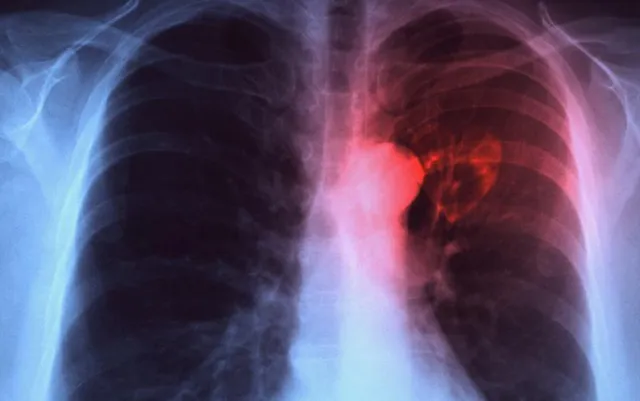

21.5 lakh TB cases reported in 2018 in India

New Delhi: In 2018, 21.5 lakh tuberculosis (TB) cases were reported to the government, as compared to 18 lakh in 2017, an increase of 17 per cent in one year. This shows better reporting and subsequent treatment, as per the Annual India TB Report for 2019 released on Wednesday.

Prime Minister Narendra Modi has announced India's revised target for ending TB by 2025, five years ahead of the Sustainable Development Goal target of 2030. India accounts for a quarter of the global TB burden with new cases in 2018 which could go up to an estimated 27 lakh.